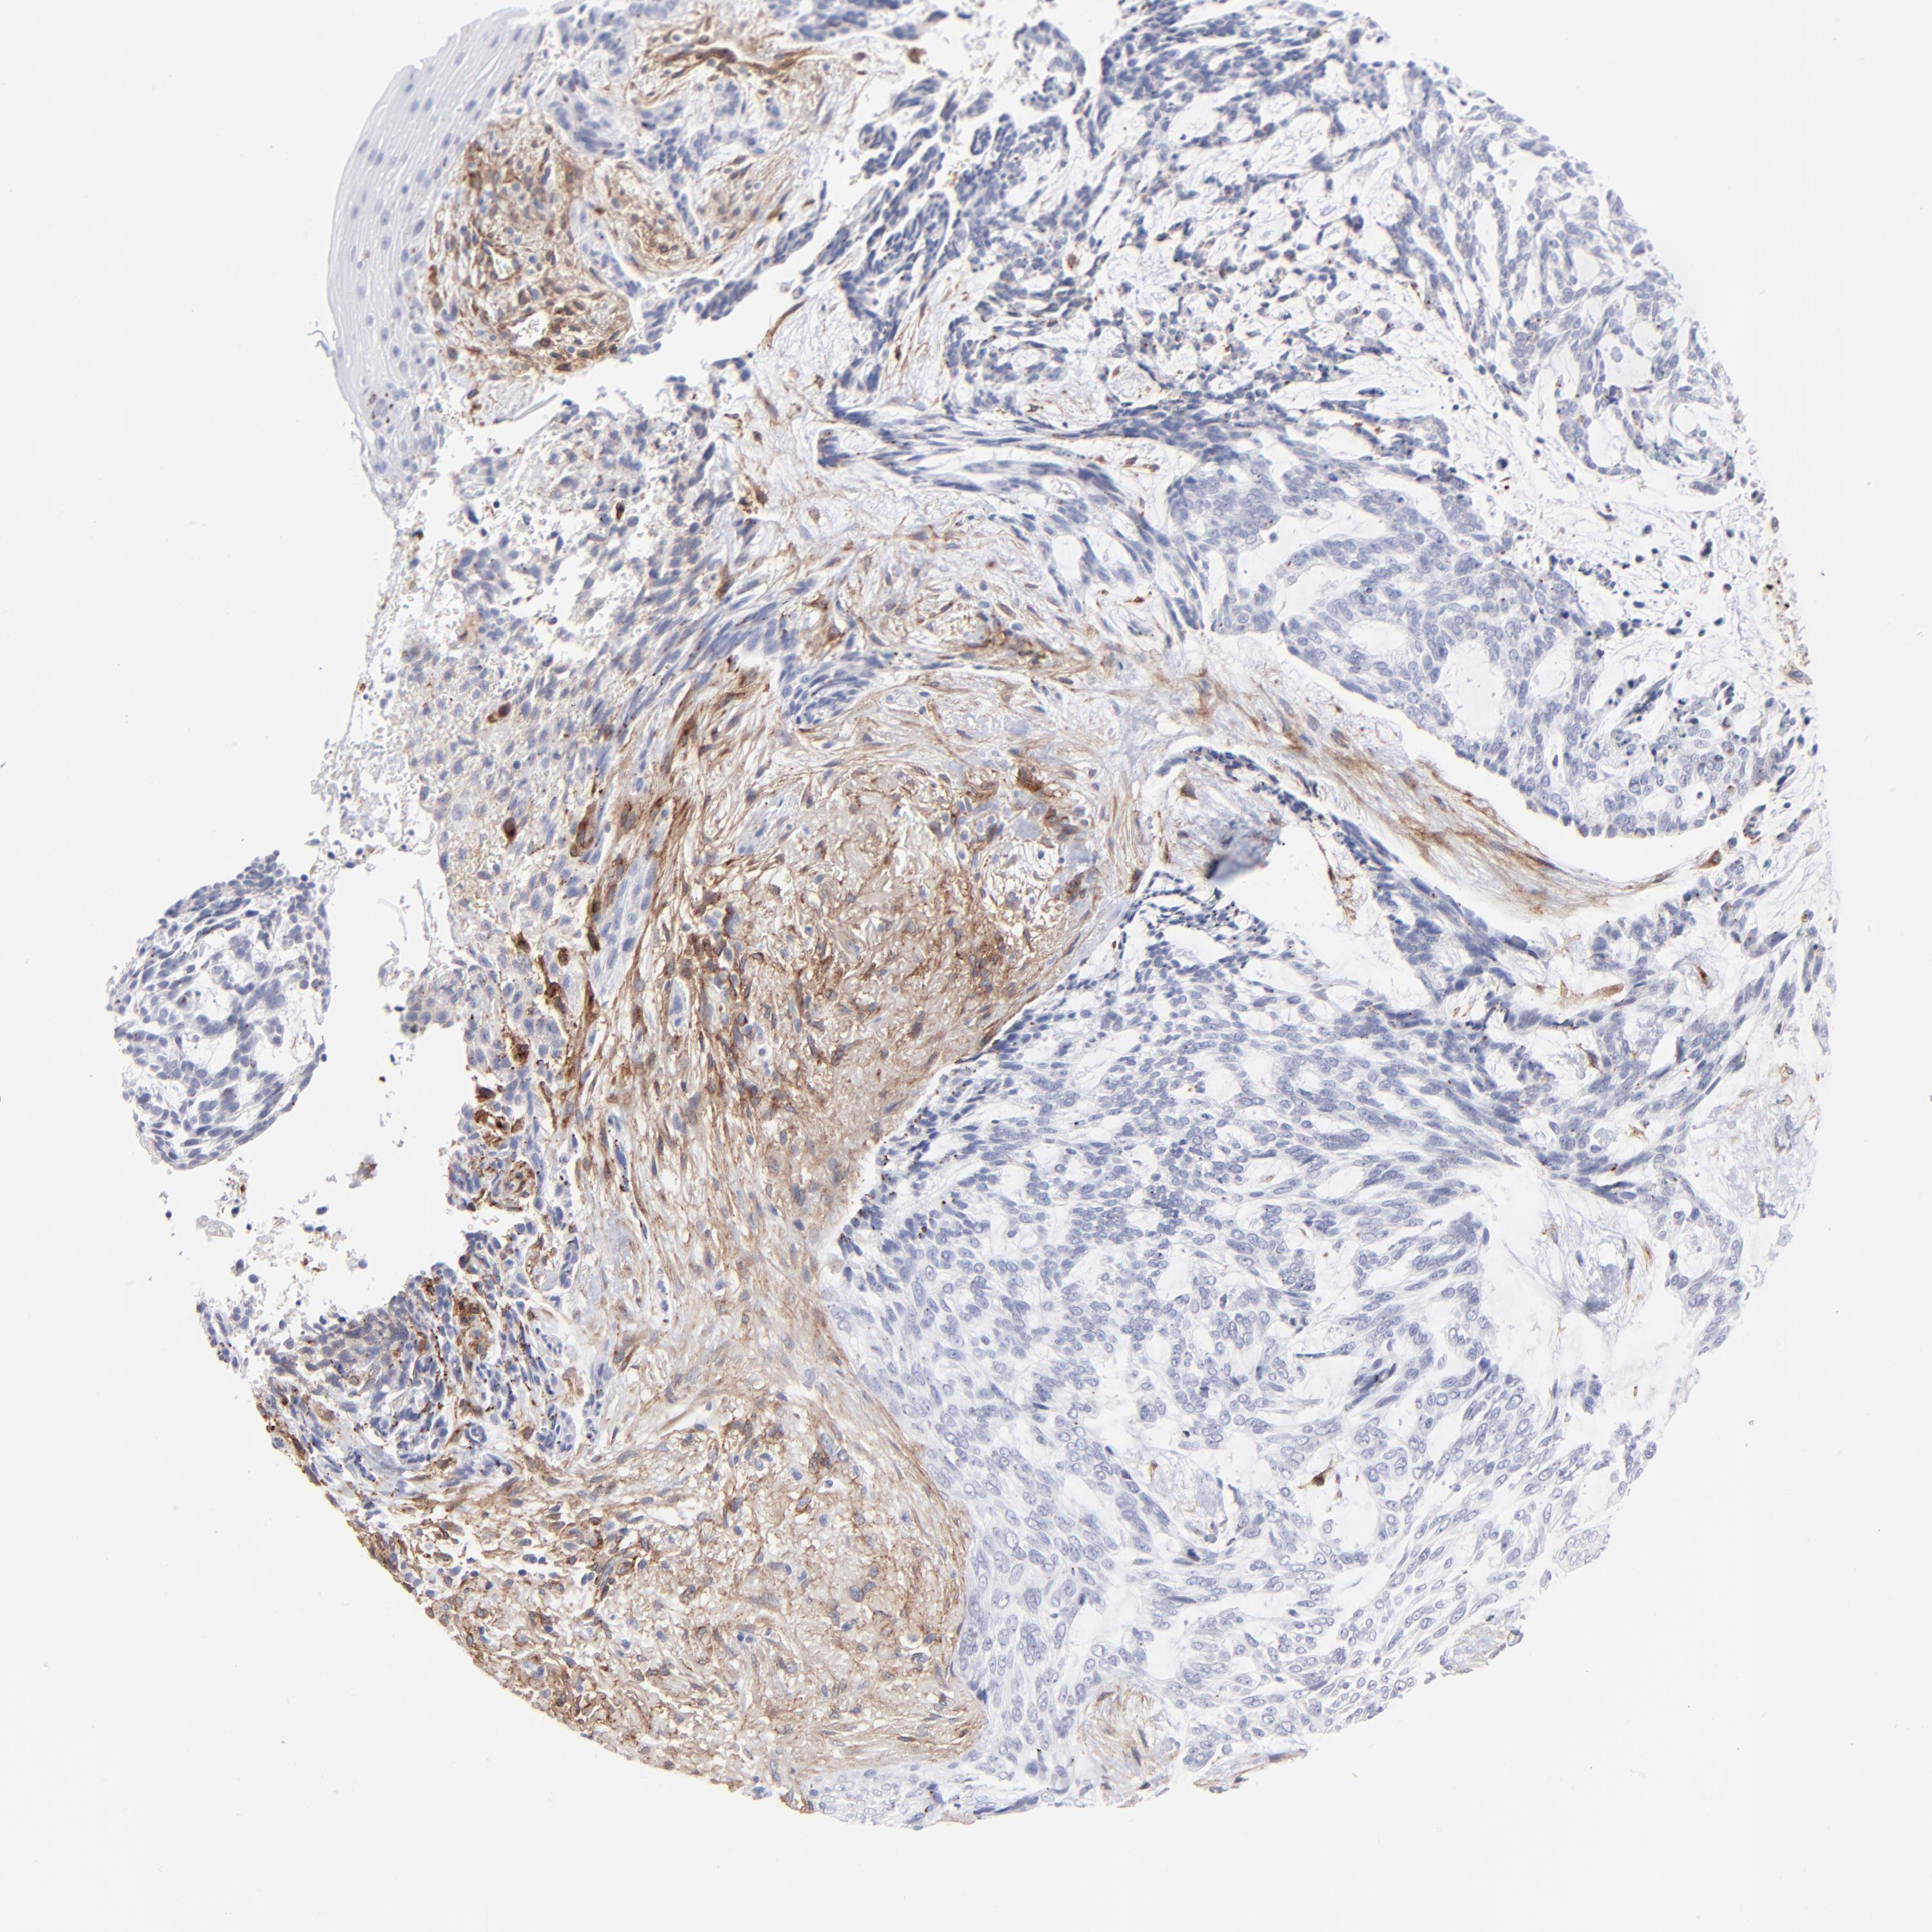

Basal cell and squamous cell cancer

SKIN CANCER - Protein expressioni

A mouse-over function shows sample information and annotation data. Click on an image to view it in a full screen mode. Samples can be filtered based on level of antibody staining by selecting one or several of the following categories: high, medium, low and not detected. The assay and annotation is described here.

Each image is clickable and will lead to virtual microscopy that enables deeper exploration of all samples and also displays staining intensity scores, fraction scores and subcellular localization as well as patient and tissue information for each sample.

Antibody CAB003842

Squamous cell carcinoma, NOS

Basal cell carcinoma

Squamous cell carcinoma in situ, NOS

Squamous cell carcinoma, metastatic, NOS